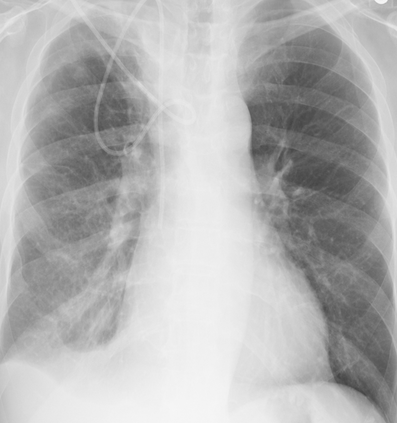

Tuberculosis remains a critical global health issue, particularly in resource-limited and remote areas. Early detection is vital for treatment, yet the lack of skilled radiologists underscores the need for artificial intelligence (AI)-driven screening tools. Developing reliable AI models is challenging due to the necessity for large, high-quality datasets, which are costly to obtain. To tackle this, we propose a teacher--student framework which enhances both disease and symptom detection on chest X-rays by integrating two supervised heads and a self-supervised head. Our model achieves an accuracy of 98.85% for distinguishing between COVID-19, tuberculosis, and normal cases, and a macro-F1 score of 90.09% for multilabel symptom detection, significantly outperforming baselines. The explainability assessments also show the model bases its predictions on relevant anatomical features, demonstrating promise for deployment in clinical screening and triage settings.